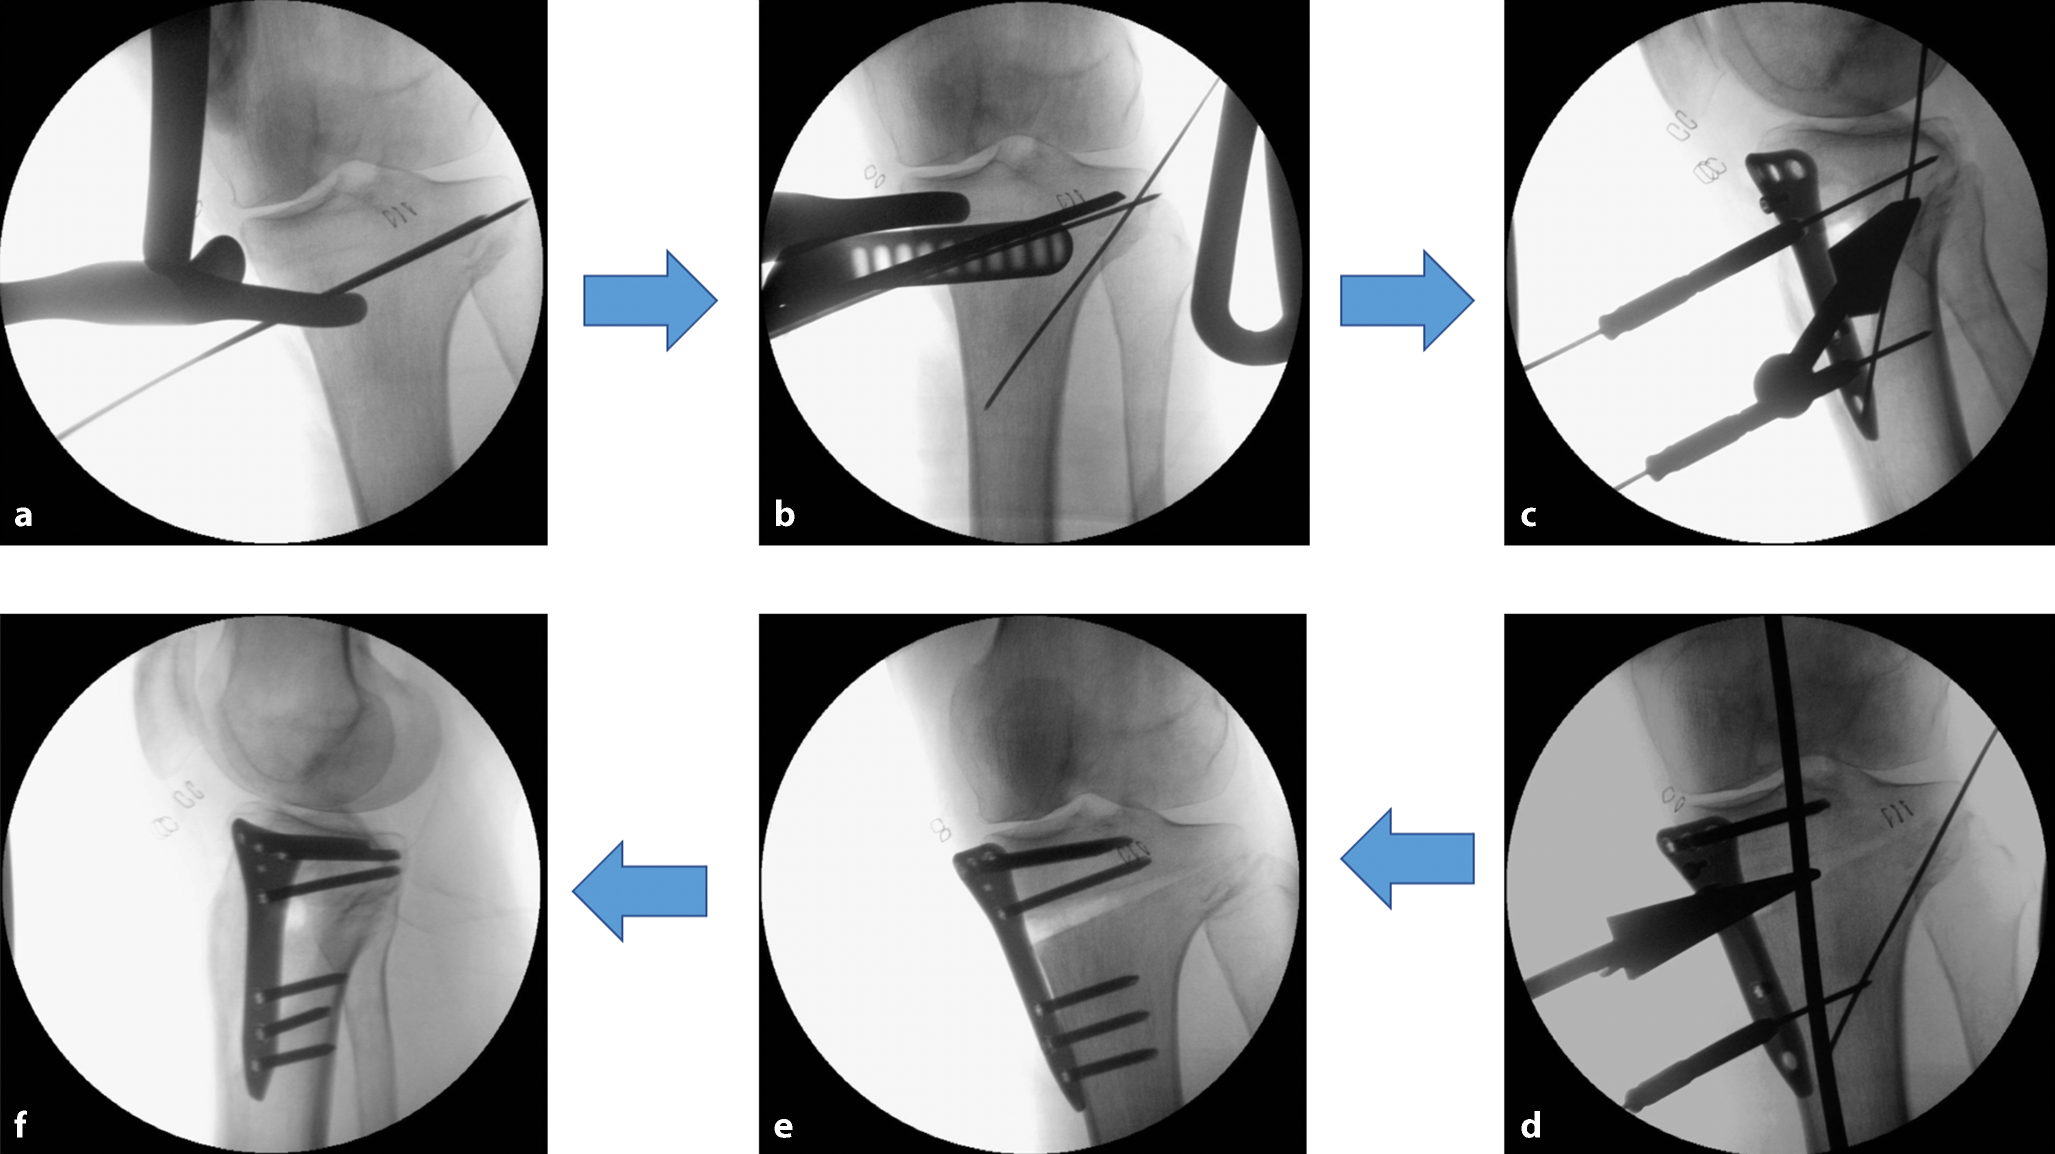

Nach diagnostischem Rundblick und Innenmeniskusteilresektion erfolgte die medial öffnende HTO kurz zusammengefasst in folgenden Schritten: Zunächst wurde die Osteotomieebene mit K‑Drähten markiert. Unter Schutz des Weichteilretraktors wurde die Osteotomie mit einem Sägeblatt durchgeführt. Der Osteotomiespalt wurde mit Osteotomiemeißeln unter Erhalt der lateralen Kortikalis aufgeklappt. Nach Öffnen des Osteotomiespalts wurde eine winkelstabile Platte ins zuvor geschaffene Plattenlager eingeschoben, ausgerichtet und unter Bildverstärker (BV)-Kontrolle positioniert. Anschließend wurden die Plattenlöcher mit winkelstabilen Schrauben schrittweise besetzt. Zuletzt erfolgte die abschließende BV-Kontrolle in 2 Ebenen (Abb. 4). Intraoperativ gab es keinen Hinweis auf eine Komplikation oder aktive Blutung.

Abb. 4

Die wichtigen Schritte der medial öffnenden HTO im Überblick. a Markierung der Osteotomieebene mit K‑Drähten, b Osteotomie mit Sägeblatt unter Schutz des Weichteilretraktors, c Öffnen des Osteotomiespalts und Anmodellieren der winkelstabilen Platte, d schrittweises Besetzen der Plattenlöcher, e abschließende BV-Kontrolle nach Fixation durch winkelstabile Platte in der anteroposterioren (a. p.) Ebene, f abschließende BV-Kontrolle nach Fixation durch winkelstabile Platte in der sagittalen Ebene